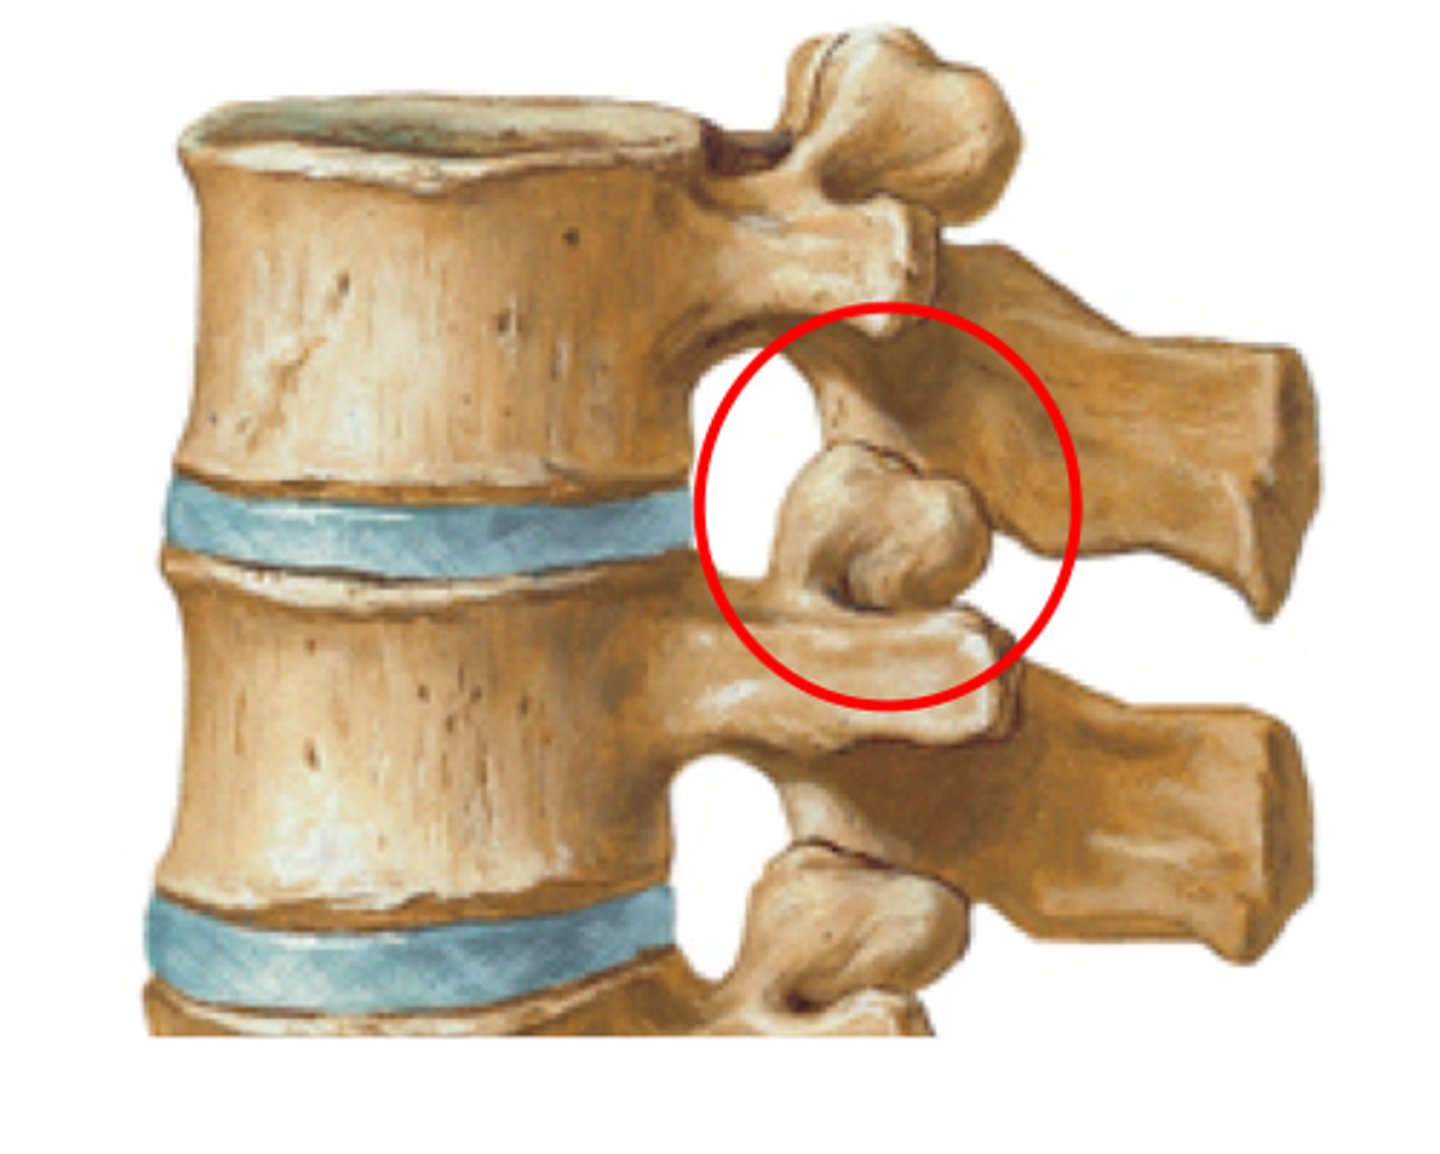

What joint do the superior and inferior articulating processes form?

zygapophyseal joint

What are the other names for the zygapophyseal joint?

apophyseal, atlantoaxial

The THORACIC zygapophyseal joints are ONLY demonstrated on what view?

70 degree oblique

The Lumbar zygapophyseal joints are ONLY demonstrated on what view?

45 degree obliques (will see "scotty dog")